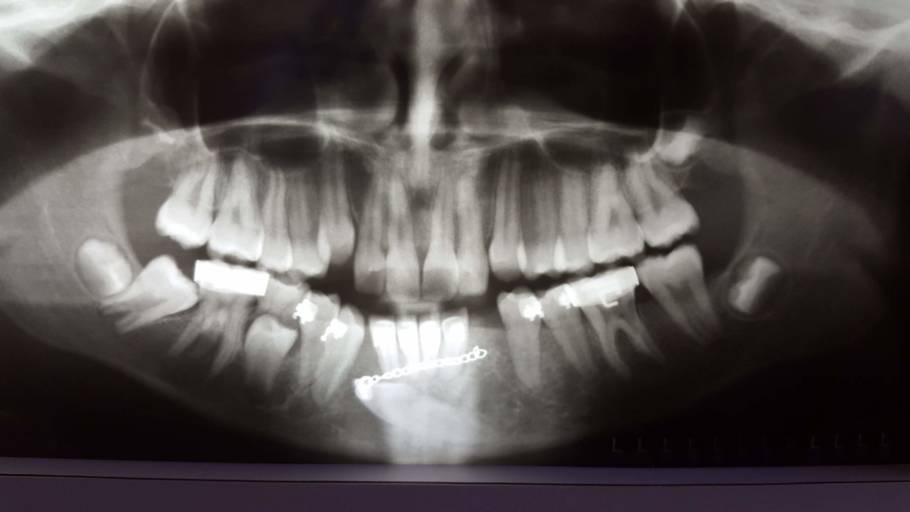

How should I fix the problem with my transmigrated mandibular canine?

I have a transmigrated mandibular canine. It is very far into my jaw. My orthodontist decided to attach a button onto the tooth, run a chain through my gums and attach it to my 2nd furthest back tooth. This constant pressure is moving the tooth into...